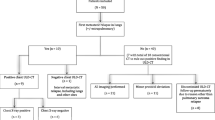

During radioactive Iodine-125 seed implantation (RISI), Iodine-125 radionuclide is implanted directly into a lesion and kills tumor cells by steadily emitting radiation. In our study, we analyzed the adverse effects of RISI for thoracic malignancy, and investigated the safety, dosage, and adverse effects of RISI for these cases. Between June 2007 and January 2018, 77 patients with thoracic recurrent and/or metastatic tumors who underwent CT-guided RISI were enrolled. Radiation-related adverse effects were analyzed, including pneumonia, esophagitis, hemorrhage, fistula, skin injury, heart injury, and spinal cord injury. We used the Common Terminology Criteria for Adverse Events (CTCAE) v4.03 to evaluate adverse effects and analyzed the relationship between adverse effects and dosimetric parameters of organs at risk (OAR), including D0.1cc, D2cc, Dmean, and V20. The results of the study were as follows: The median follow-up period was 11 months. The median postoperative dose (D90) was 122 Gy (45.7–241.8 Gy). Three patients (3.9%) showed radiation pneumonitis of grade ≥2. Two patients (2.6%) showed radiation-induced esophagitis of grade ≥2. One patient (1.3%) showed an esophageal fistula. Two patients (2.6%) had a tracheal fistula. Five patients (6.5%) had radiation-related skin reactions. One patient (1.3%) reported chest wall pain, while three (3.9%) showed hemoptysis. No patients showed radiation myelitis or cardiotoxicity. The mean D2cc of organs at risk were 165.7 Gy (lung), 10.61 Gy (esophagus), 10.25 Gy (trachea), 18.07 Gy (blood vessel), 12.64 Gy (heart), 14.77 Gy (spinal cord), 17.47 Gy (skin). Dosimetric parameters, such as D0.1cc, D2cc and Dmean, were higher in patients with toxic reactions (above the upper limit of 95% confidence interval among the overall data). Chi-square test showed that skin D0.1cc > 600 Gy, D2cc > 500 Gy, and Dmean >90 Gy were associated with grade ≥2 radiation dermatitis (p < 0.05), but no clear dose-toxicity correlation was found in other OARs. So, we concluded that the overall incidence of toxicity and adverse effects from RISI for the treatment of thoracic tumors is low. The dose-toxicity characteristics have not been fully defined. Doses within the upper limit of the 95% confidence interval may be considered safe. This was a retrospective analysis, and follow-up period was minimal, indicating possible limitations of this study.

The incidence of adverse reactions was low: 3 patients (3.9%) had radiation pneumonitis of grade ≥2, including two (2.6%) grade 2 cases and one (1.3%) grade 3 case, all of which occurred within 3 months of RISI. Two patients (2.6%) had radiation esophagitis of grade ≥2, including one (1.3%) grade 2 case and one (1.3%) grade 3 case, which occurred 4 months and 5 months after RISI, respectively. One (1.3%) patient developed an esophageal fistula 5 months after implantation. Two (2.6%) patients had a tracheal fistula, which developed 5 and 9 months after the operation. Five (6.5%) patients had grade 2 radiation-induced skin reactions, all of which occurred within 6 months of implantation. One (1.3%) patient developed chest wall pain within two months. Three (3.9%) patients had hemoptysis, which occurred 1, 6, and 10 months after implantation. None of the patients showed radiation myelitis and cardiotoxicity (Table 3). Chi-square test showed that high skin dose (D0.1cc > 600 Gy, D2cc > 500 Gy, and Dmean >90 Gy) was associated with grade ≥2 radiation dermatitis (p < 0.05), but no dose-toxicity correlation was found in other OARs (Table 4).